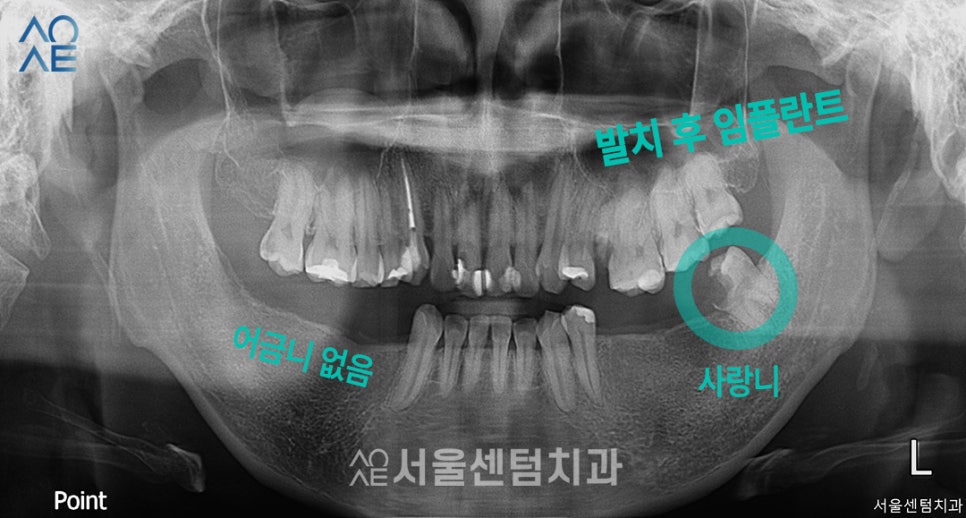

위 이미지는 구강검진을 위해 첫 내원했을 때

촬영한 엑스레이 사진입니다.

다른곳에서 치료를 받은 치아도 보이고

어금니를 상실한 부분도 보였습니다.

전체적으로 치료할 부분이 많이 보여서

상세 내용은 아래 표에서 설명드리겠습니다.

(엑스레이에선 왼/오가 반대로 나옵니다)

| 🦷현재 상태 &치료 계획🦷 |

|---|

| (1) 현재 상태🔹 오른쪽 아래 어금니는 아예 없음🔹 왼쪽 아래 사랑니는 깨져서 치아 기능을 할 수 없음🔹전체적으로 잇몸이 내려가있음 |

| (2) 치료 계획🔹왼쪽 사랑니 발치🔹왼쪽 위 / 오른쪽 아래 어금니 임플란트 식립 |